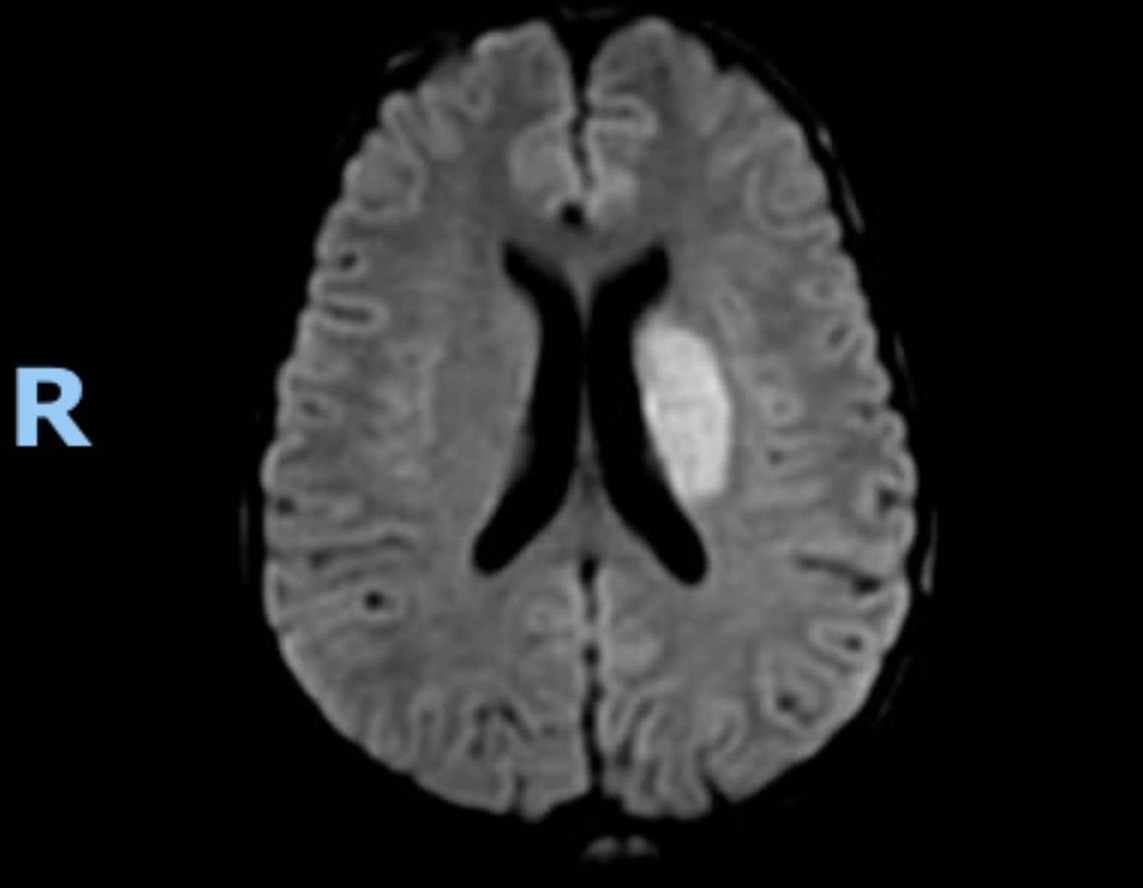

20 tuổi bị đột quỵ do sử dụng thuốc gây nghiện

Một bệnh nhân trẻ ngoài 20 tuổi bị đột quỵ trên tiền căn sử dụng thuốc gây nghiện. Mặc dù nhiều khuyến cáo được truyền thông rộng rãi, các trường hợp thực tế đã xảy ra, nhưng nhiều người trẻ vẫn xem nhẹ mối nguy hại của chất gây nghiện.